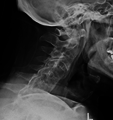

-

Lateral X-ray of the neck in ankylosing spondylitis